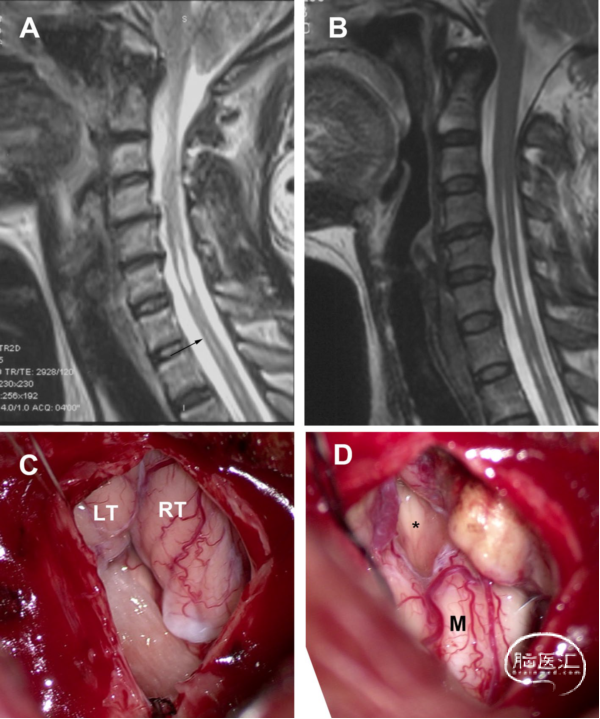

女性,72岁,有8年的四肢麻木和无力病史。术前MRI显示,髓内裂伴CM。术中可见萎缩的扁桃体占据枕骨大孔并覆盖在Magendie孔上。扁桃体低功率双极电凝烧灼后收缩复位,Magendie孔暴露,未观察到隔膜。但手术后症状并未缓解(图5)。

图5. 萎缩型CM-SM病例。A. 术前MRI显示,髓内裂伴CM-I。B. 术后MRI显示,SM的大小保持稳定。C. 打开硬脑膜后,见扁桃体萎缩,占据枕骨大孔和覆盖Magendie孔。D. 扁桃体低功率双极电凝烧灼后收缩复位,Magendie孔暴露,未观察到隔膜。